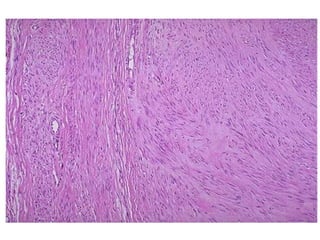

Fibroma /

Fibrotecoma